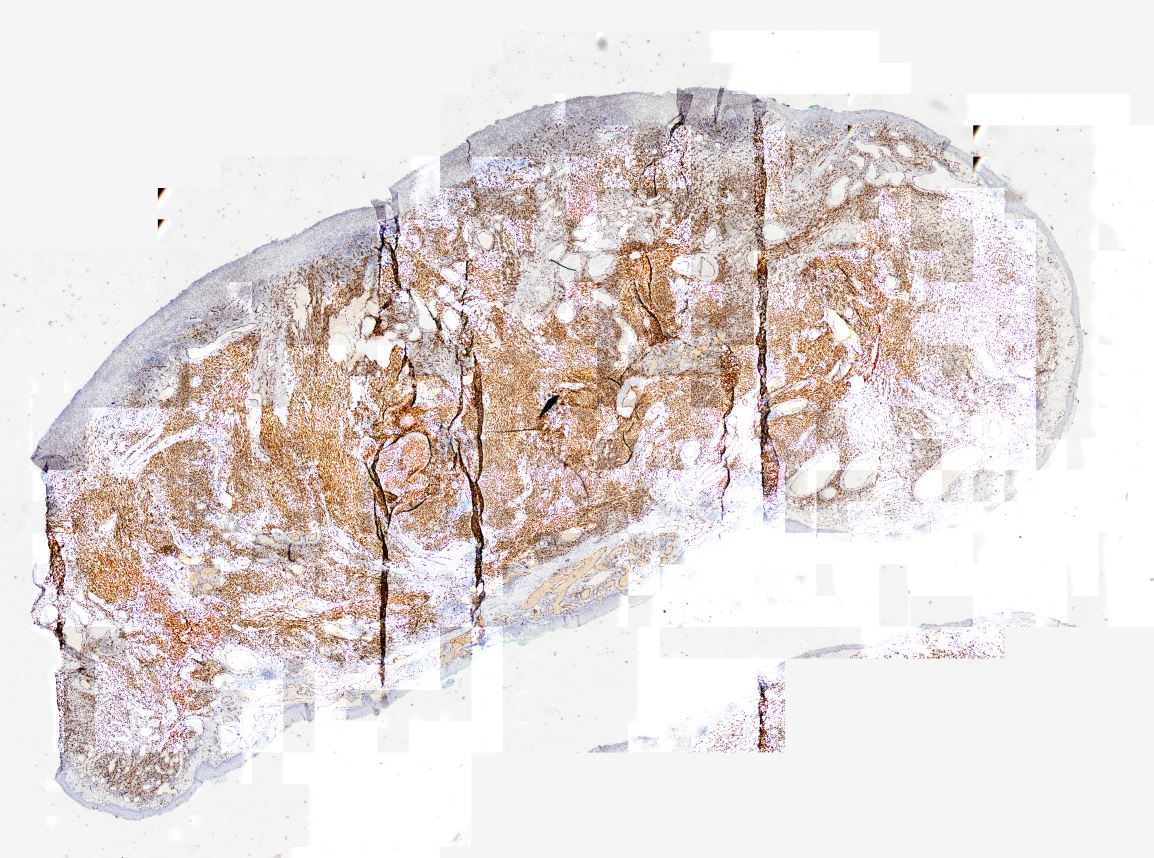

Medüller tiroid karsinomu Medüller tiroid karsinomu, HE

Medüller tiroid karsinomu Medüller tiroid karsinomu, Kalsitonin pozitifliği

Medüller tiroid karsinomu Medüller tiroid karsinomu, Trioglobulin

Medüller tiroid karsinomu Sinaptofizin Medüller tiroid karsinomu Sinaptofizin